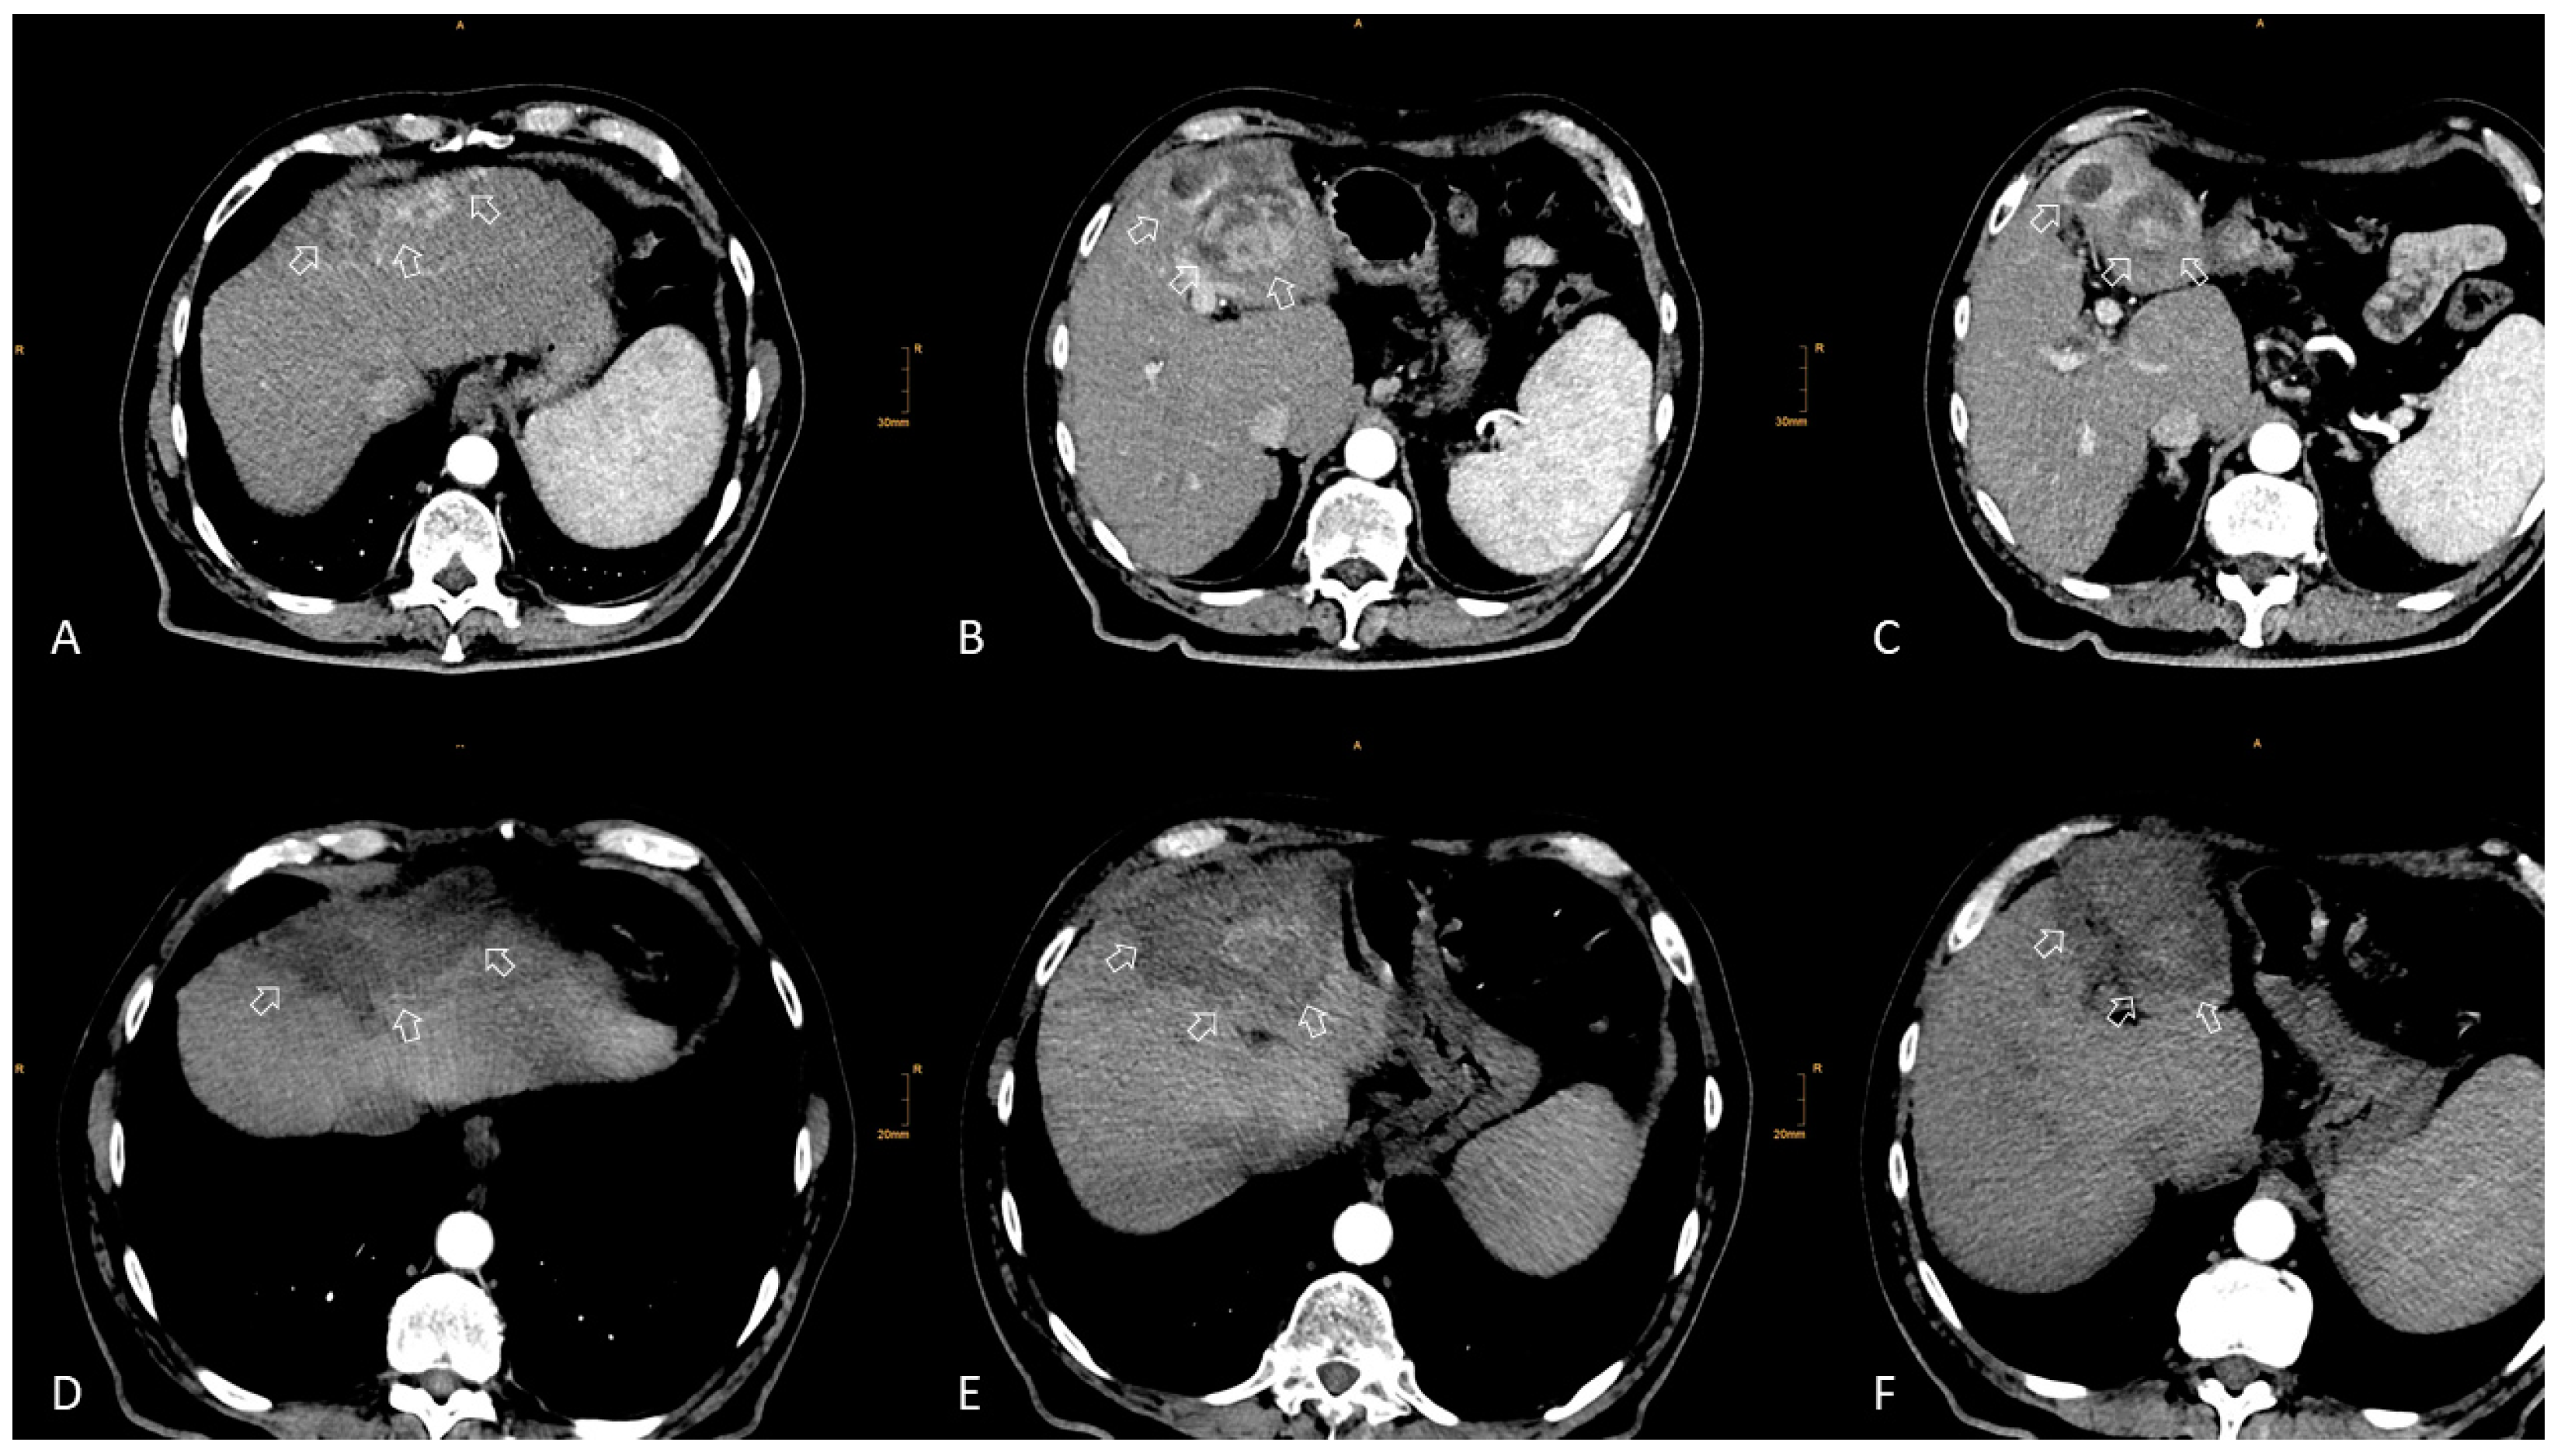

2. Local Ablation

2.1. Eastern Perspective

2.2. Western Perspective